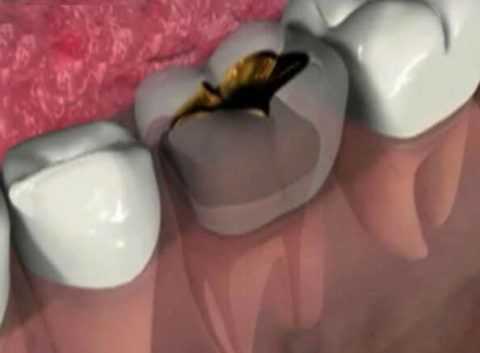

Источник инфицирования кости - это бактерии околозубных тканей, радикулярные кисты и опухолеподобные процессы челюстей. Самой распространенной причиной остеомиелита является периодонтит больших коренных зубов.

![Гнойный периодонтит нижней челюсти]()